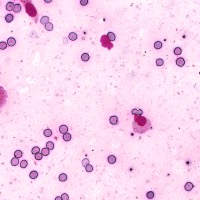

Medical Diagnosis: The "4class" model can be employed by pathologists to accurately identify and quantify the different cell types in blood and tissue samples, assisting in the diagnosis of various blood disorders and diseases, including anemia, leukemia, and infections.

Research and Drug Development: Researchers can use the "4class" model to analyze cellular response to experimental treatments, providing essential data for drug discovery, evaluating the efficacy of novel compounds, and understanding cell behavior under various conditions.

Education and Training: The "4class" computer vision model can serve as an educational tool for medical students and professionals, facilitating their understanding of different cell types, their characteristics, and functions, while promoting accurate identification in laboratory settings.

Automated Screening: Integration of the "4class" computer vision model into medical laboratory equipment can automate the process of cell classification during screenings or biopsies. This can help save time and reduce the risk of human errors during the evaluation of samples.

Telemedicine and Remote Analysis: The "4class" model can support telemedicine platforms, making it possible for healthcare professionals to remotely access and evaluate blood and tissue samples. This would be particularly useful in underserved areas, where access to pathologists might be limited.